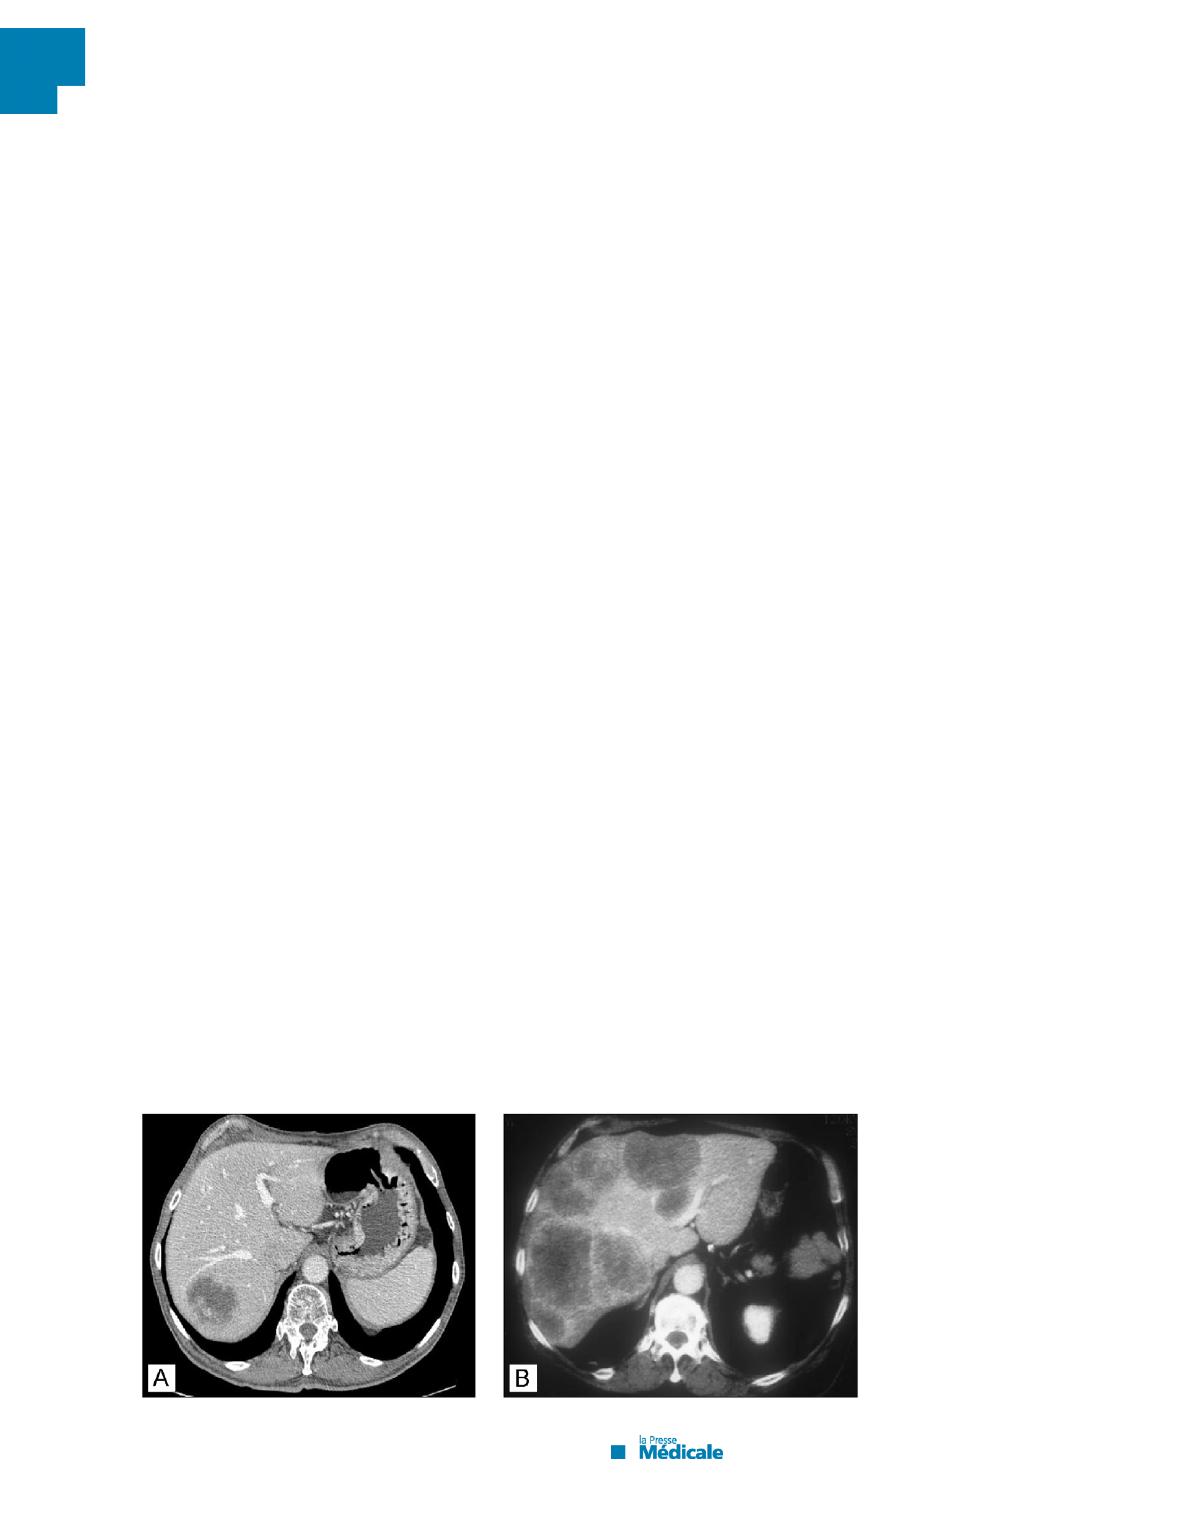

Figure

1

Métastase

hépatique

unique

du

secteur

postérolatéral

foie

droit

résécable

d’emblée

(classe

I)

(A).

Métastases

mutiples

volumineuses

et

bilobaires

potentiellement

II)

(B)